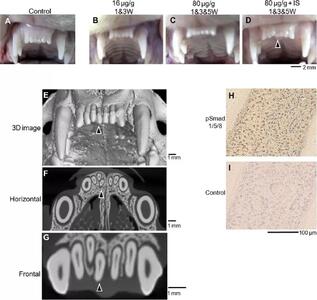

اندیشه معاصر - انقلاب در علم پزشکی/ احیای بینایی با استفاده از پیوند سلول های بنیادی برای نخستین بار در جهان اندیشه معاصر

دانشمندان ژاپنی توانستهاند با پیوند سلولهای بنیادی گرفته شده از سلولهای خونی انسان، بینایی را به افرادی که دچار آسیب قرنیه شدهاند، بازگردانند.